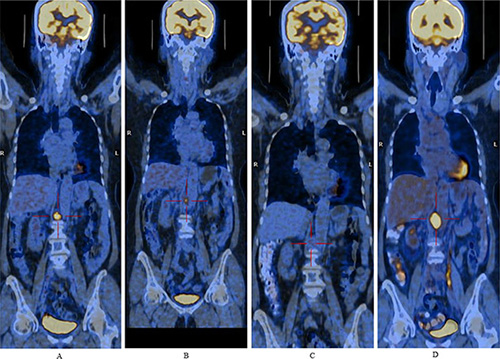

During the safety extension phase, 15 patients received at least one dose of enzastaurin. Disease progression was the major cause of withdrawal from the study. Anti-tumor response was evaluated in 14 patients, including 4 with solid tumors and 10 with lymphoma. One 40-year-old female with relapsed DLBCL who received enzastaurin after a complete response following salvage chemotherapy was disease free for 30 months, and was still using the study drug at the last follow-up on June 18, 2015. A partial response was observed in a 70-year-old female patient with DLBCL whose disease had relapsed after first-line R-CHOP (rituximab, cyclophosphamide, doxorubicin, vincristine and prednisone) therapy and two cycles of salvage chemotherapy with R-GEMOX (rituximab, gemcitabine and oxaliplatin) and R-IMED (rituximab, ifosfamide, methotrexate, etoposide and dexamethasone). The duration of this partial response was 8.1 months (Figure 1). Stable disease was observed in five lymphoma patients, lasting for 22.1 months in one Hodgkin lymphoma (HL) patient and 25.2 months in one follicular lymphoma patient. Four solid tumor patients (two with nasopharyngeal carcinoma, one with rectal cancer, and one with breast cancer) and the remaining three lymphoma patients experienced progressive disease.

Figure 1: Positron emission computer tomography images demonstrate lymphadenopathy post-crura of the right diaphragm from a relapsed diffuse large B-cell lymphoma patient. Figure 1A, Figure 1B, Figure 1C and Figure 1D were images of baseline and after 1.8 months, 6.5 months, 9.9 months of enzastaurin treatment, respectively. A partial response was observed after 1.8 months of treatment and lasted for 8.1 months.